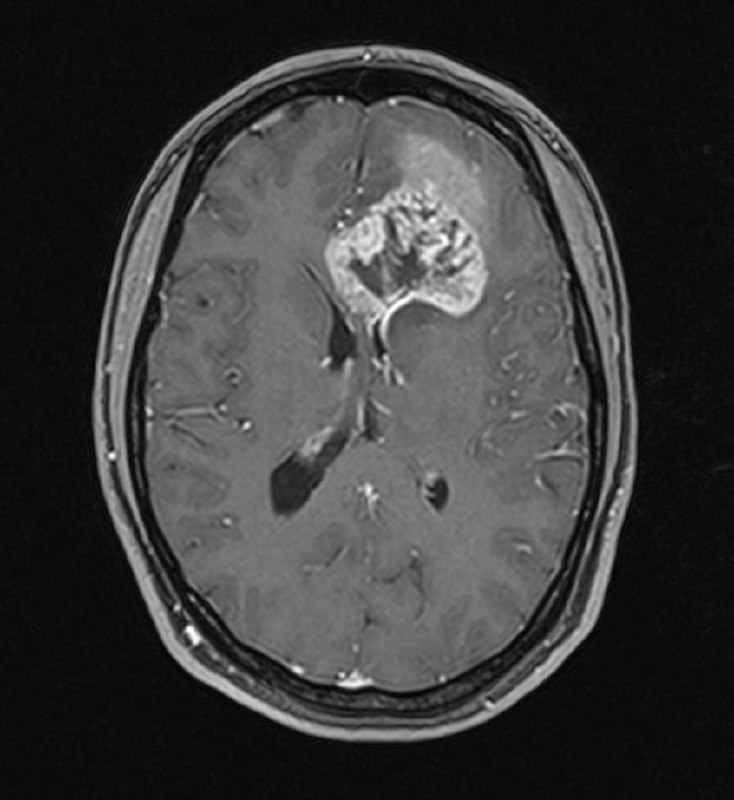

Глиобластома.

Разница в две недели.

Отек стал меньше из-за стероидов.

Но растет быстро, сволочь…